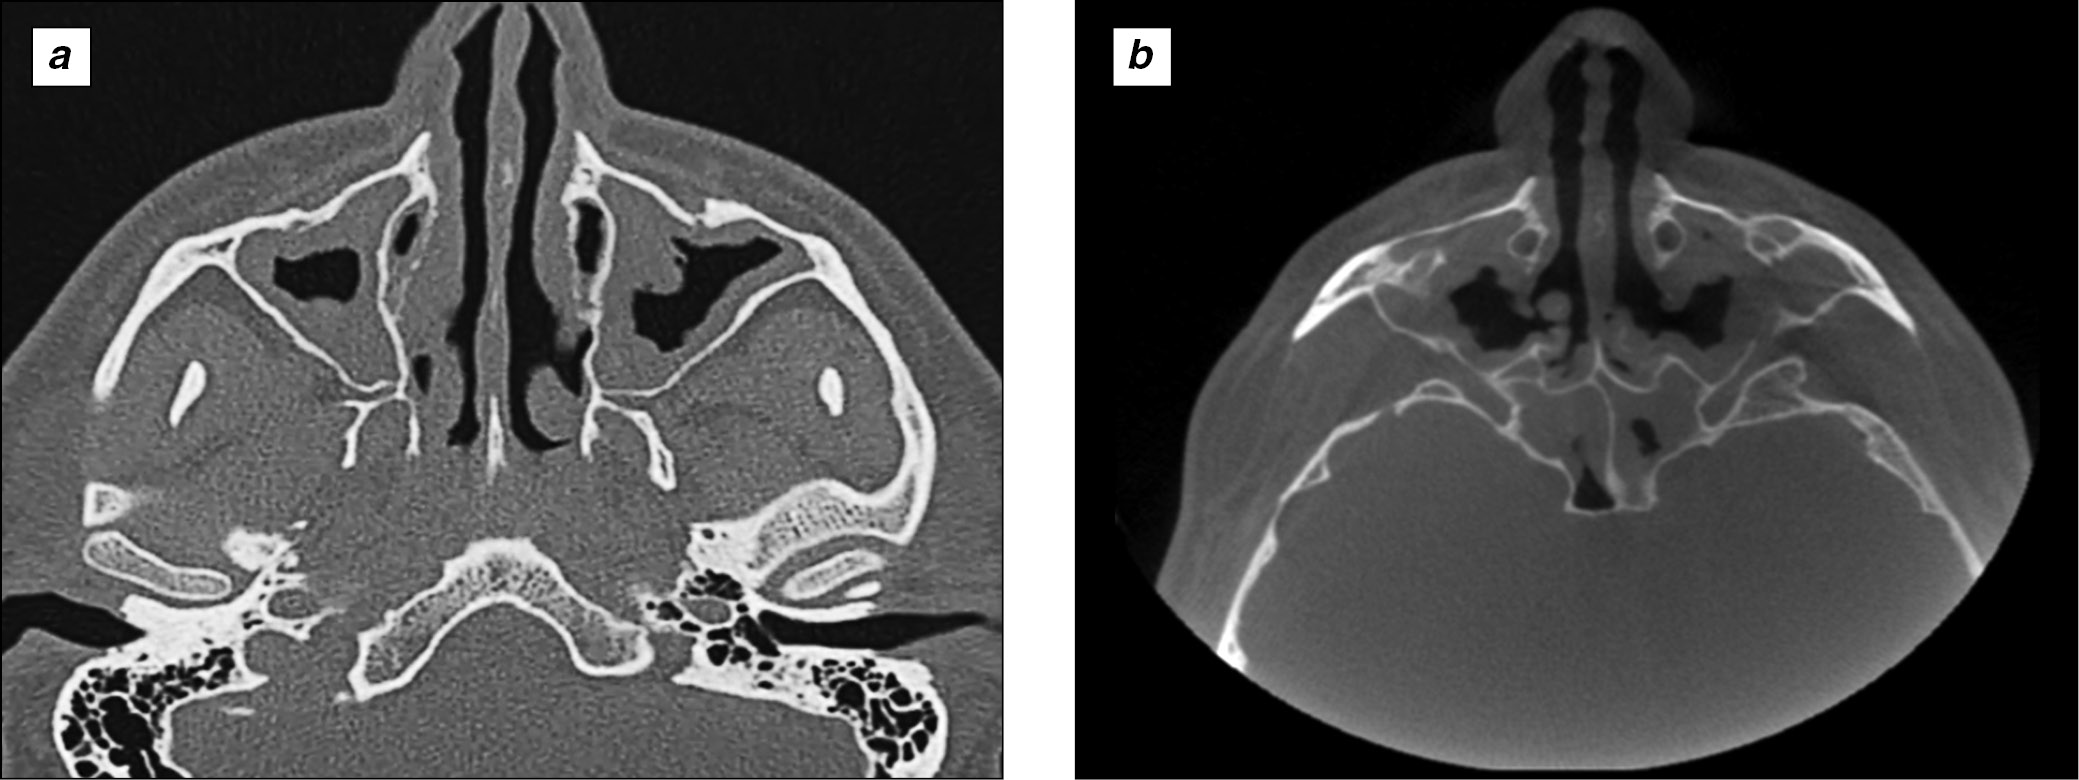

КТ околоносовых пазух (рис. 2, а): визуализируются полипозно-воспалительные изменения слизистых оболочек, на фоне которых воздушность околоносовых пазух снижена тотально и субтотально. Естественные соустья верхнечелюстных пазух обтурированы. По медиальным стенкам обеих верхнечелюстных пазух определяются костные дефекты (постоперационные). В перегородке определяется дефект. Стенки ячеек решётчатого лабиринта прослеживаются фрагментарно.

Рис. 2. Динамика симптомов полипозного риносинусита по данным компьютерной томографии околоносовых пазух (сентябрь 2018 – сентябрь 2020 г.): a ― снимок после проведённой эндоскопической полисинусотомии в сентябре 2018 г. (полипозные разрастания в верхнечелюстных, клиновидных пазухах, в клетках решётчатого лабиринта); b ― снимок через 24 мес от старта анти-IgE-терапии (сохраняется только пристеночное утолщение слизистой оболочки в верхнечелюстных, клиновидных пазухах, в клетках решётчатого лабиринта с восстановлением воздушности в околоносовых пазухах)

Fig. 2. The dynamics of rhinosinusitis with nasal polyps according to paranasal sinuses CT scan (September 2018 – September 2020): a ― image after endoscopic polysinusotomy was performed in September 2018 (polypous mass in maxillary, sphenoidal sinuses, in ethmoid sinuses); b ― image 24 month from the start of anti-IgE therapy (only parietal mucosal thickening in maxillary, sphenoidal sinuses, in ethmoid sinuses with airness restoration in paranasal sinuses).